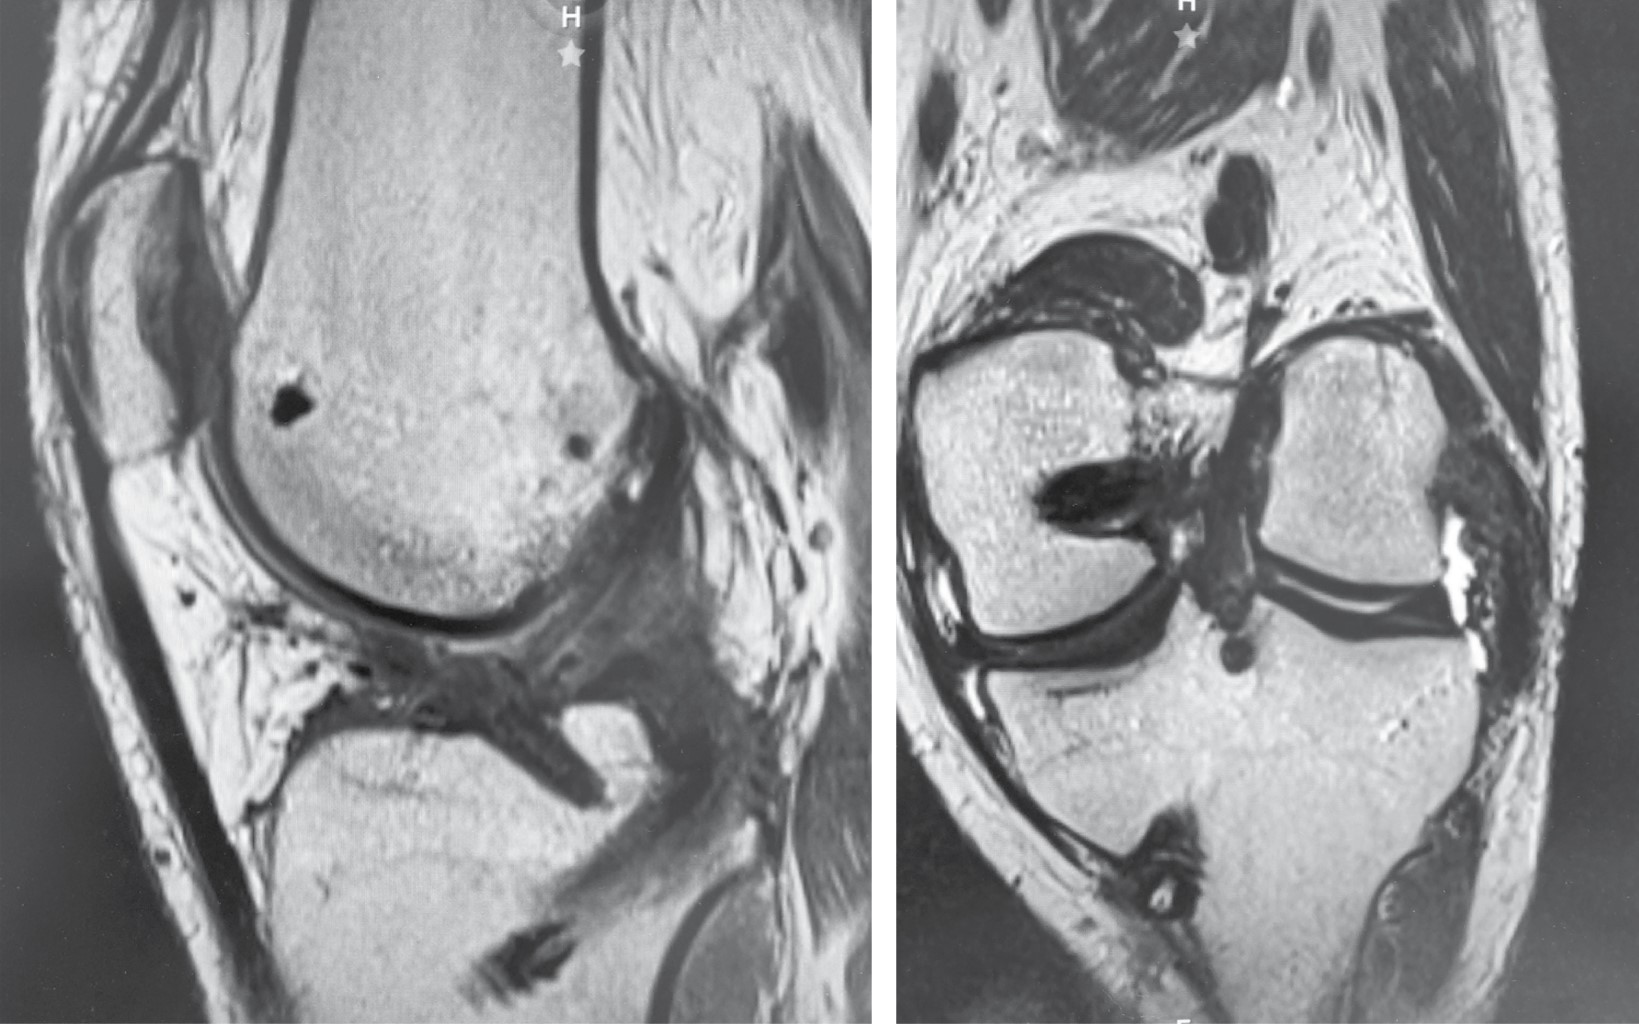

Introduction: Anterior cruciate ligament injuries are common, however, tibial avulsions in adults are rare. The gold standard continues to be reconstruction either by allograft or autologous graft. Primary repairs in femoral side lesions have been reported in recent years by bioabsorbable anchors. Case report: We present the case of a primary repair of anterior cruciate ligament due to tibial avulsion in a patient 19 years after presenting direct trauma with added lesions of posterior cruciate ligament and posterolateral corner. Primary repair was performed by trans-tendon portal with suture of the anterior cruciate ligament crossed by FiberTape and FiberWire with a SwiveLock anchor (4.75 mm) in tibial footprint. Results: Twelve months after surgery is with independent gait, full range of movement, with clinical rating scales, Tegner before injury and post-injury at 6, Lysholm 91, 73.6 subjective IKDC, objective IKDC in C and EQ-5D 0.79. Conclusion: Fixation with bioabsorbable anchor is possible in the avulsion of the post-traumatic tibial spine.

Figure 2